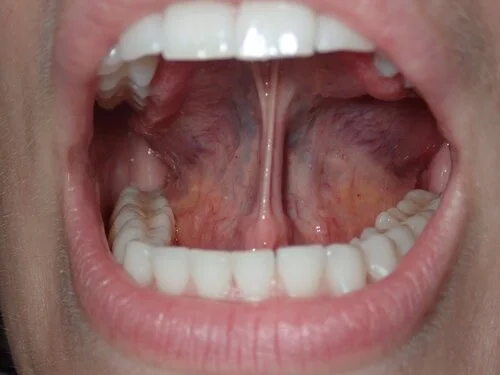

Prior to Lingual Frenectomy (tongue-tie release) and post 6 sessions of Myofunctional Therapy to strengthen, coordinate, and prep the tongue for release.

During the release the patient stated at one part of the procedure she felt her tongue instantly had more lift and movement along with the chronic tension in her neck felt reduced.

case study image of cave pre release

case study image of tongue lift pre release